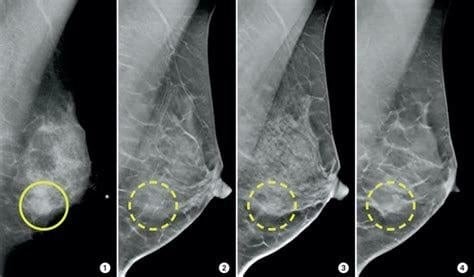

These posts are often accompanied with an image showing the mammograms of swollen lymph nodes in breasts. The claims can be found on Facebook (here and here), and Twitter. These posts combined were shared over 200 times.

Clinical assistant professor Michael Tiong-Hong Co at HKU’s Department of Surgery said, “it is impossible to interpret the images shown on the website as what we [medical doctors] usually do is to compare bilateral mammograms.”

But Annie Lab found that the photo attached in the claim on Facebook does not show mammograms after COVID-19 vaccination.

Through reverse image search, the same mammogram image was found in an article published by Sunnybrook Magazine in 2016. The article said that 3D mammograms were introduced to improve breast cancer screening.

Another image attached in the misleading tweet came from a news report by Fox News about a new guideline to avoid false positive results of breast cancer following COVID-19 vaccination.